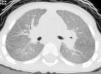

A la edad de 30 meses (en la que el último episodio se había producido 2 meses antes), se obtuvo una radiografía de tórax durante un periodo de mantenimiento de un buen estado en el gemelo con unos antecedentes clínicos más graves, y se observó una afectación alveolar intersticial persistente; la TCAR reveló una atenuación de la imagen de vidrio esmerilado, con patrón intersticial y nódulos finos (fig. 1).